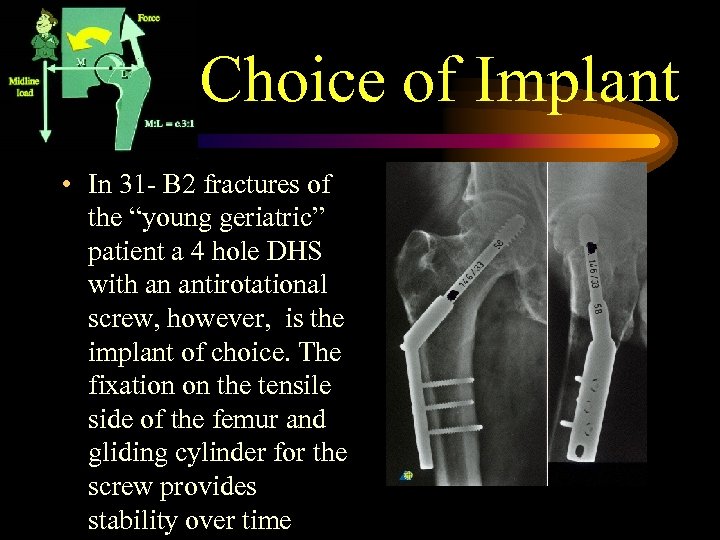

Choice of Implant • In 31 - B 2 fractures of the “young geriatric” patient a 4 hole DHS with an antirotational screw, however, is the implant of choice. The fixation on the tensile side of the femur and gliding cylinder for the screw provides stability over time

Choice of Implant • In 31 - B 2 fractures of the “young geriatric” patient a 4 hole DHS with an antirotational screw, however, is the implant of choice. The fixation on the tensile side of the femur and gliding cylinder for the screw provides stability over time